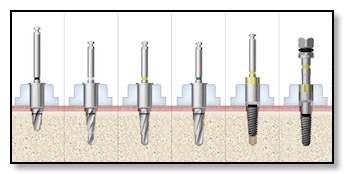

Placement of Dental Implants and Bone Integration

Now that the surgical guide is ready, placing the implant in your jawbone is pretty quick. To make sure the surgery goes smoothly, Dr. Tsai might prescribe a round of antibiotics before placing the implant. The actual placement, along with a confirmatory CT scan to double-check its position, usually takes about an hour. Dr. Tsai will numb the area with local anesthesia, use the surgical guide to line things up perfectly, use different bone drills, and secure the implant in place. Depending on your situation, she might attach a healing cap right away or use a smaller cover screw for healing later on. It takes around four to five months for the implant to integrate with the surrounding bone, a process called bone integration or healing. The exact duration depends on things like your oral cavity chemistry, any medications you're taking, and your overall health.